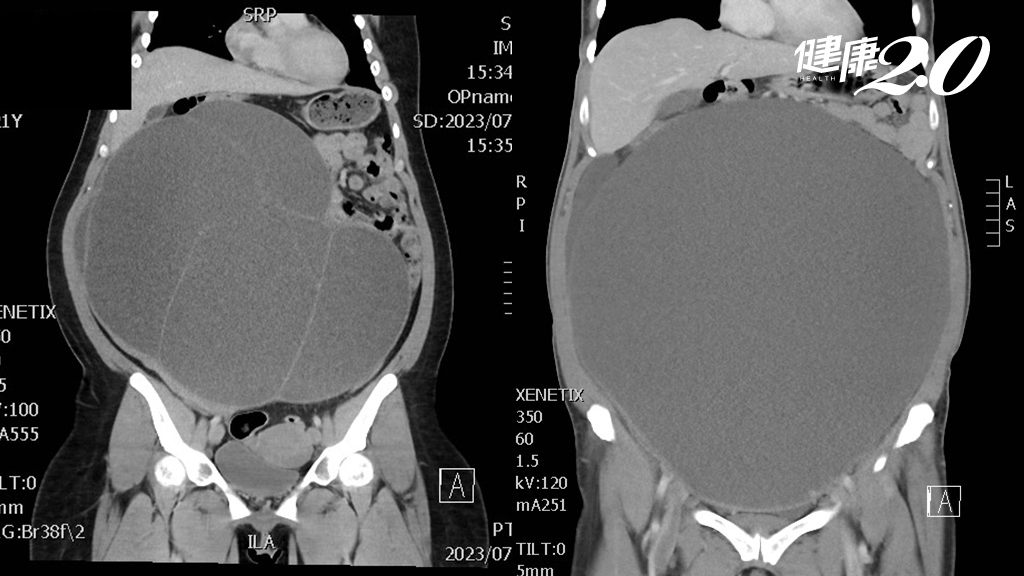

日前有兩名60歲及21歲女性都因為肚子越來越大到屏基就醫,經過超音波、電腦斷層檢查發現兩位都罹患卵巢囊腫,且腫瘤已經有30公分大小,隨後進行單孔腹腔鏡手術將腫瘤切除取出,順利出院。